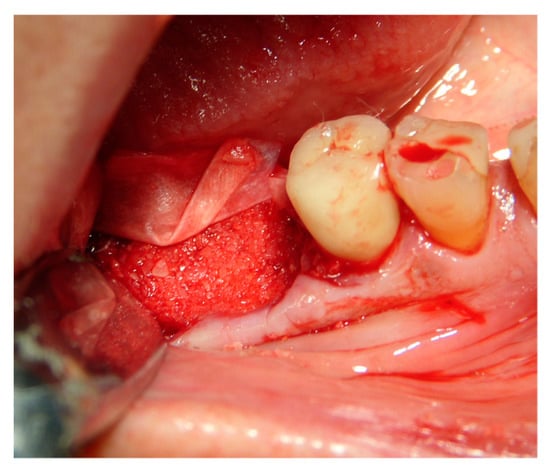

The faraway graft procedure follow up is 40 months and the near graft procedure follow up is 9 months (Average 24.5 months). The faraway implant follow up is 35 months and the near implant follow up is five months. The success rate of the tooth graft procedure is 99.1% (one site was infected and lost the regeneration and the implant) (Figure 6, Figure 7 and Figure 8). In all cases, after the all implants were inserted, complete osseointegration after proper healing period was achieved. After the healing period, hard and soft tissues were stable (Figure 9, Figure 10 and Figure 11). The healing of soft tissues after grafting procedures was particularly free of complications. The implant success rate was 98.94% (one implant failed).

Figure 7. Dental element 46 to be extracted with the need for ridge maintenance due to an extensive interradicular defect.

Applsci 09 05396 g007

Figure 8. Ridge maintenance through the use of the extracted element and cover with a resorbable membrane.